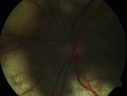

Ocular Lymphoma - Initially presented like auto-immune retinopathy280 views43 year old man: initial presentation - The vision in the left eye is blurry and opaque for about 2 weeks. In the central of the vision, when he covers the right eye, in the center of the left eye there is a film with a light in the middle. This has never happened before. He has not been sick for the last few months. A few weeks ago he saw waves on the floor when looking down but that has gone away. Since the vision loss started the vision has not changed much. The central vision is not getting better. Â

Labs normal. One positive antiretinal antibody - Arrestin

VA improved over 2 months to normal. Then the patient had 2 more episodes of self-limited vision loss (no treatment). Then 2 years later he presented with a diagnosis of CNS lymphoma and later developed subretinal deposits (last images)Oct 25, 2021